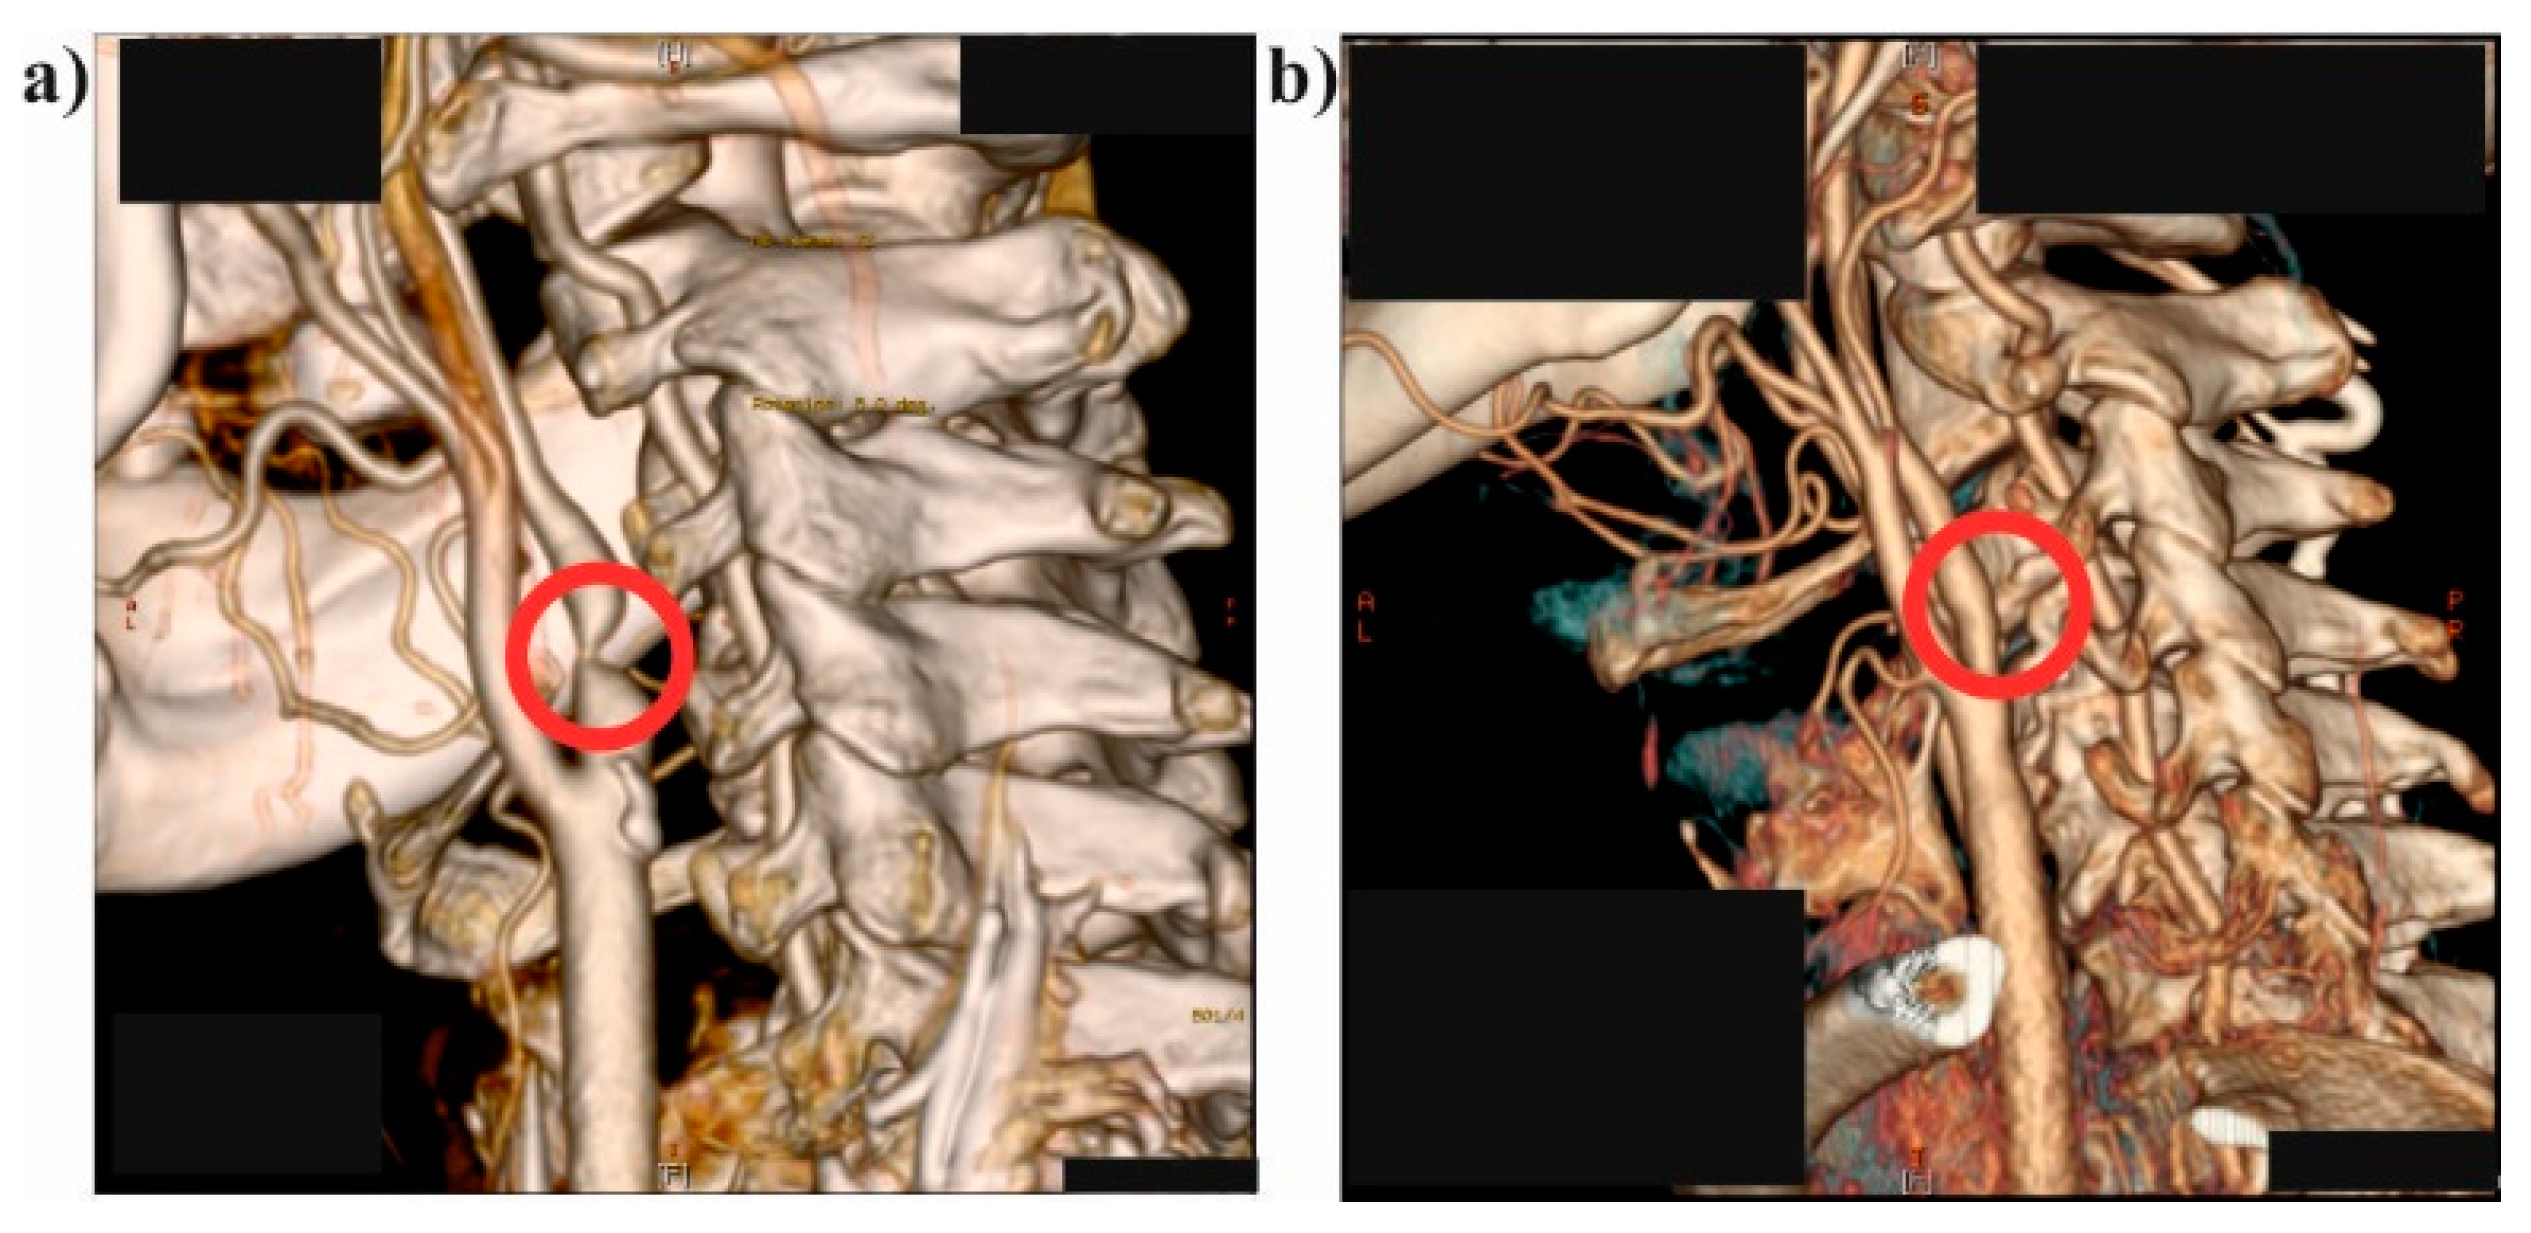

2.1. Medical Data